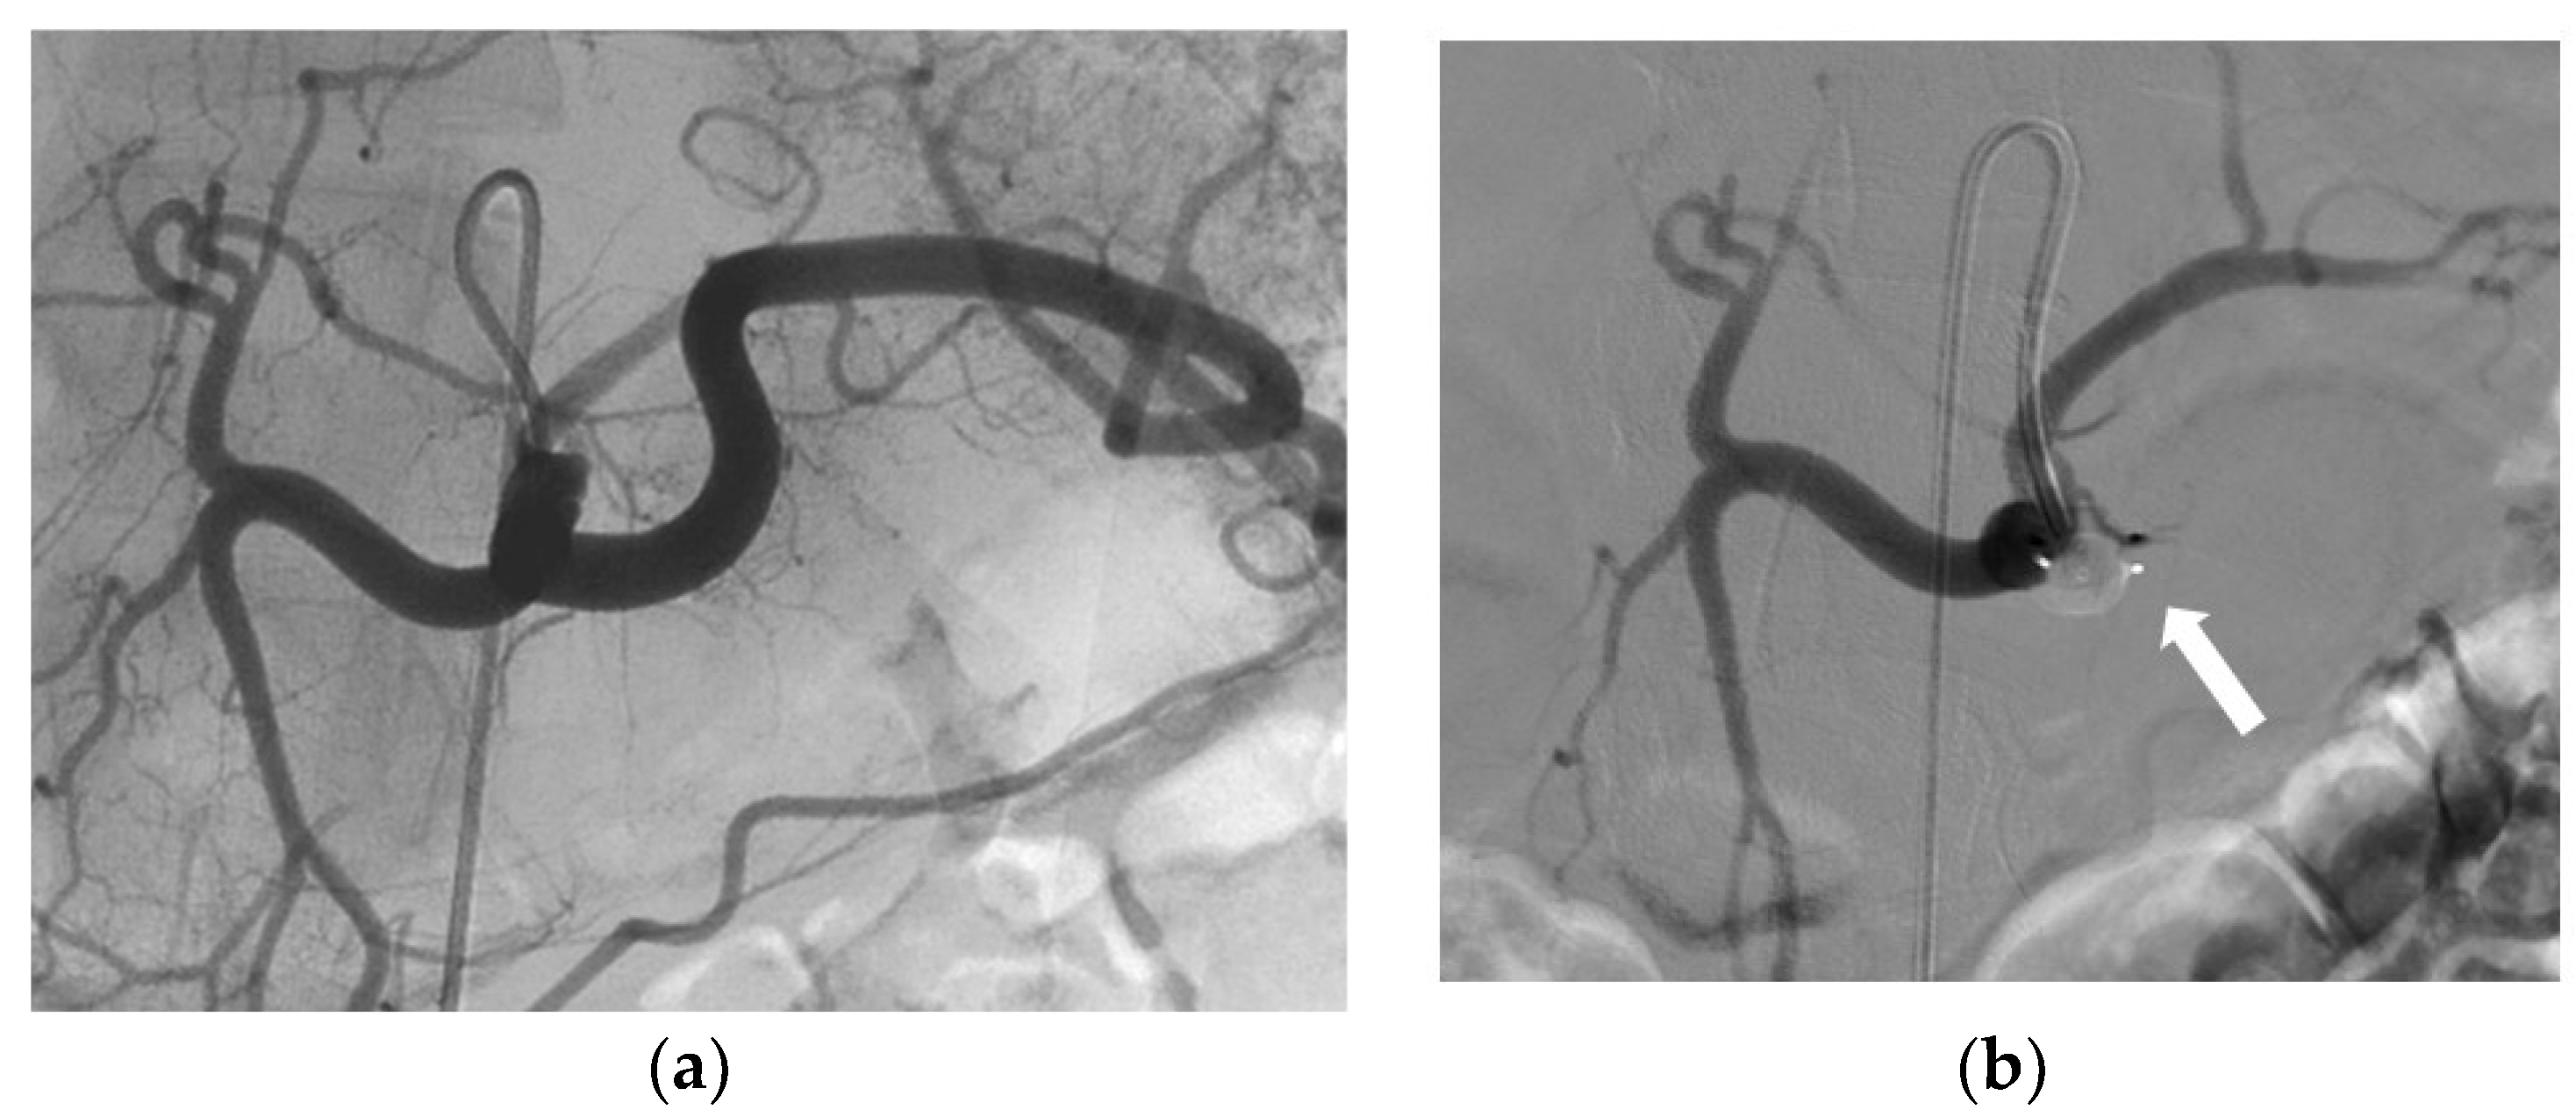

3.2. Indications and Techniques

3.3. Effectiveness